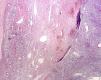

Pure renal sarcomas are rare; sometimes they are related to the renal capsule or blood vessels and a few cases of osteosarcoma have been reported. We report an unusual case of renal osteosarcoma in an 80-year-old man who underwent nephrectomy for pyelo-ureteral stenosis and hydronephrosis. The tumor was hemorrhagic and attached to the pyelocaliceal surface. Histopathology revealed a pleomorphic neoplasm with features of telangiectatic osteosarcoma. No areas of transitional or renal cell carcinoma or other sarcomatous component were present. Relevant features, such as calcifications and osseous metaplasia, were present at the implantation zone of the tumor. The present case differs from previously reported ones as it was an unexpected finding observed in a non-functioning kidney with good clinical behavior and corresponded to an unusual morphologic variant of osteosarcoma, the telangiectatic type. Finally, the relation with areas of calcification and ossification poses interesting questions as to its histogenenis.

Los sarcomas renales son raros y en ocasiones se relacionan con la cápsula renal o vasos sanguíneos. Dentro de este grupo se han descrito algunos casos de osteosarcoma. En este artículo describimos un caso peculiar de osteosarcoma renal. Un varón de 80 años fue sometido a nefrectomía por estenosis pieloureteral e hidronefrosis. Se observó un tumor hemorrágico adherido a la superficie pielocalicial. Microscópicamente mostró características histológicas propias de osteosarcoma telangiectático. No asociaba áreas de carcinoma urotelial o renal ni otro componente sarcomatoso. Un dato relevante fue la presencia, en la zona de implantación del tumor, de calcificaciones distróficas y focos de osificación heterotópica. El presente caso difiere de los anteriormente publicados. Fue un hallazgo incidental, en un riñón no funcionante, y ha mostrado buen comportamiento clínico. Histológicamente correspondía a la variante telangiectática de osteosarcoma. Por último, la relación con áreas de calcificación y osificación plantea posibles implicaciones histogenéticas.